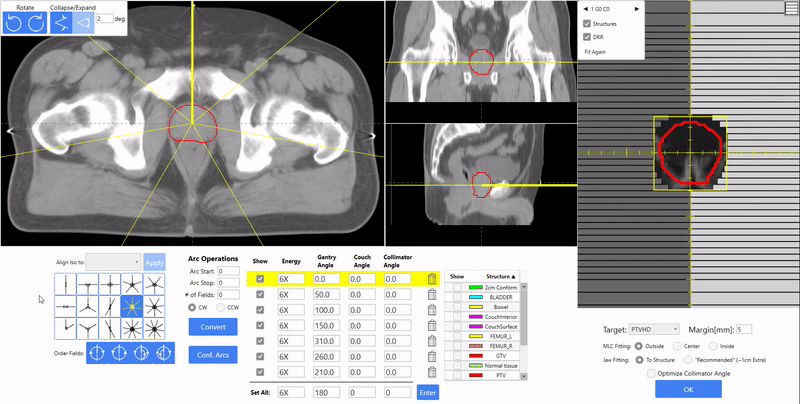

Pelvis Planning

Still using wedges for 3-field rectum plans? EZFluence can automatically generate the fluence or field-in-field segments for the lateral beams. Compatible with single energy or mixed energies.